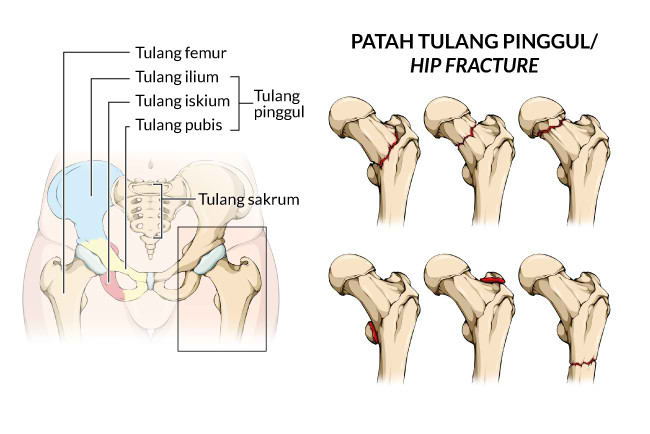

Patah Tulang Pinggul - Gejala, penyebab dan mengobati - Alodokter

Patah Tulang Pinggul - Gejala, penyebab dan mengobati - Alodokter